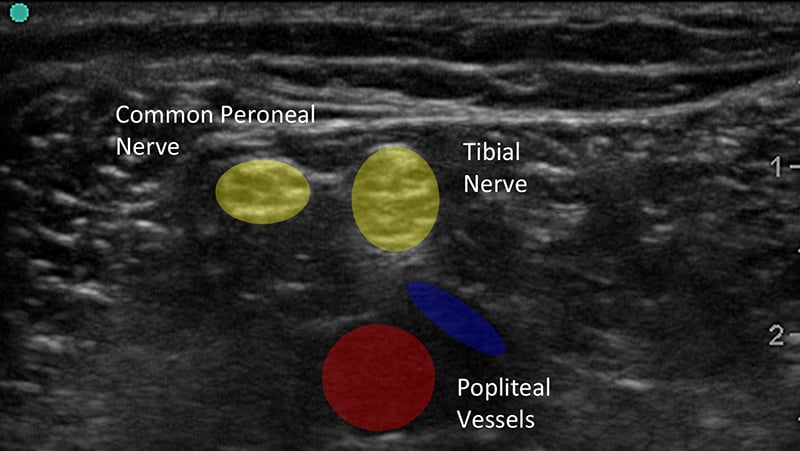

Figure 1b. Ultrasound Image of Peripheral Nerves With Labels

- Classically, nerves have a honeycomb-like appearance in cross section caused by bundling of hypoechoic nerve fascicles within hyperechoic peri- and endoneurium.

- Distal or smaller nerves contain smaller amounts of myelinated axons and can instead look like the cut end of a rope and mimic the appearance tendons.

- Nerves may be oval, round or triangular and often change shape along their course.

- Nerves are often found by their association with more easily identified structures such as blood vessels, bone or muscles.